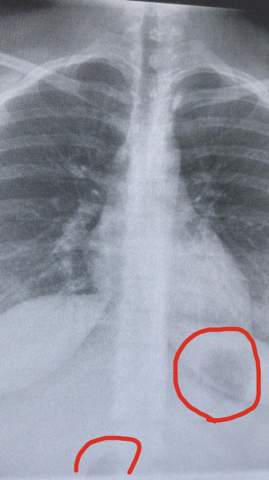

Bei Zahntraumata benötigen wir Röntgenbilder um festzustellen ob der Zahn durch die Krafteinwirkung frakturiert ist oder ob sich noch Zahnsplitter oder Wurzelreste im Knochen befinden. Auf dem Röntgenbild einer gesunden Lunge zeigt sich das Organ scharf abgegrenzt gegenüber anderen Organen und Knochen.

So kann man Hinweise auf mögliche Erkrankungen erkennen. Teilweise kann ein Tumor im Röntgen dargestellt werden bevor die ersten Symptome auftreten. Die Umrisse der Lunge auf dem Bild schwarz sind gut zu erkennen ebenso die des Herzens und Zwerchfells beides weiß. Bei genauerem Hinsehen lassen sich seitlich des Brustbeins sogar die Verästelungen der Bronchien sehen. Auf dem Röntgenbild einer gesunden Lunge zeigt sich das Organ scharf abgegrenzt gegenüber anderen Organen und Knochen. Auf dem Röntgenbild ist das Lungeninfiltrat als helle verdichtete Struktur erkennbar. Damit lässt sich unter anderem feststellen ob ein Knochen gebrochen ist.